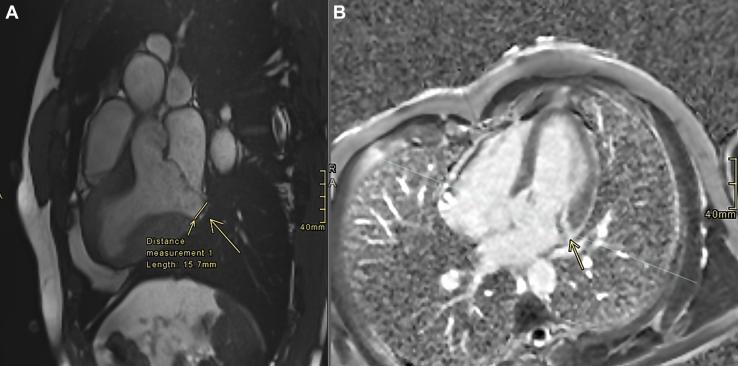

Sudden cardiac arrest during flight in a military helicopter pilot with mitral annular disjunction.

https://cdn.ncbi.nlm.nih.gov/pmc/blobs/c0aa/12432881/8c33375eb627/gr1.jpg